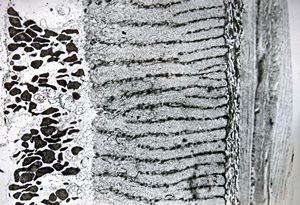

Oxyuris vermicularis - muscular wall